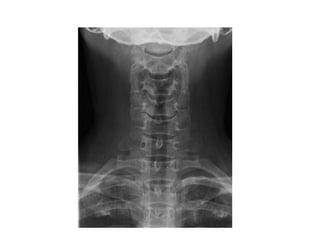

INCIDÊNCIA COLUNA CERVICAL

AP

ESTRUTURAS MAIS DEMONSTRADAS: Espaços articulares, corpos vertebrais e

processos espinhosos.

PERFIL